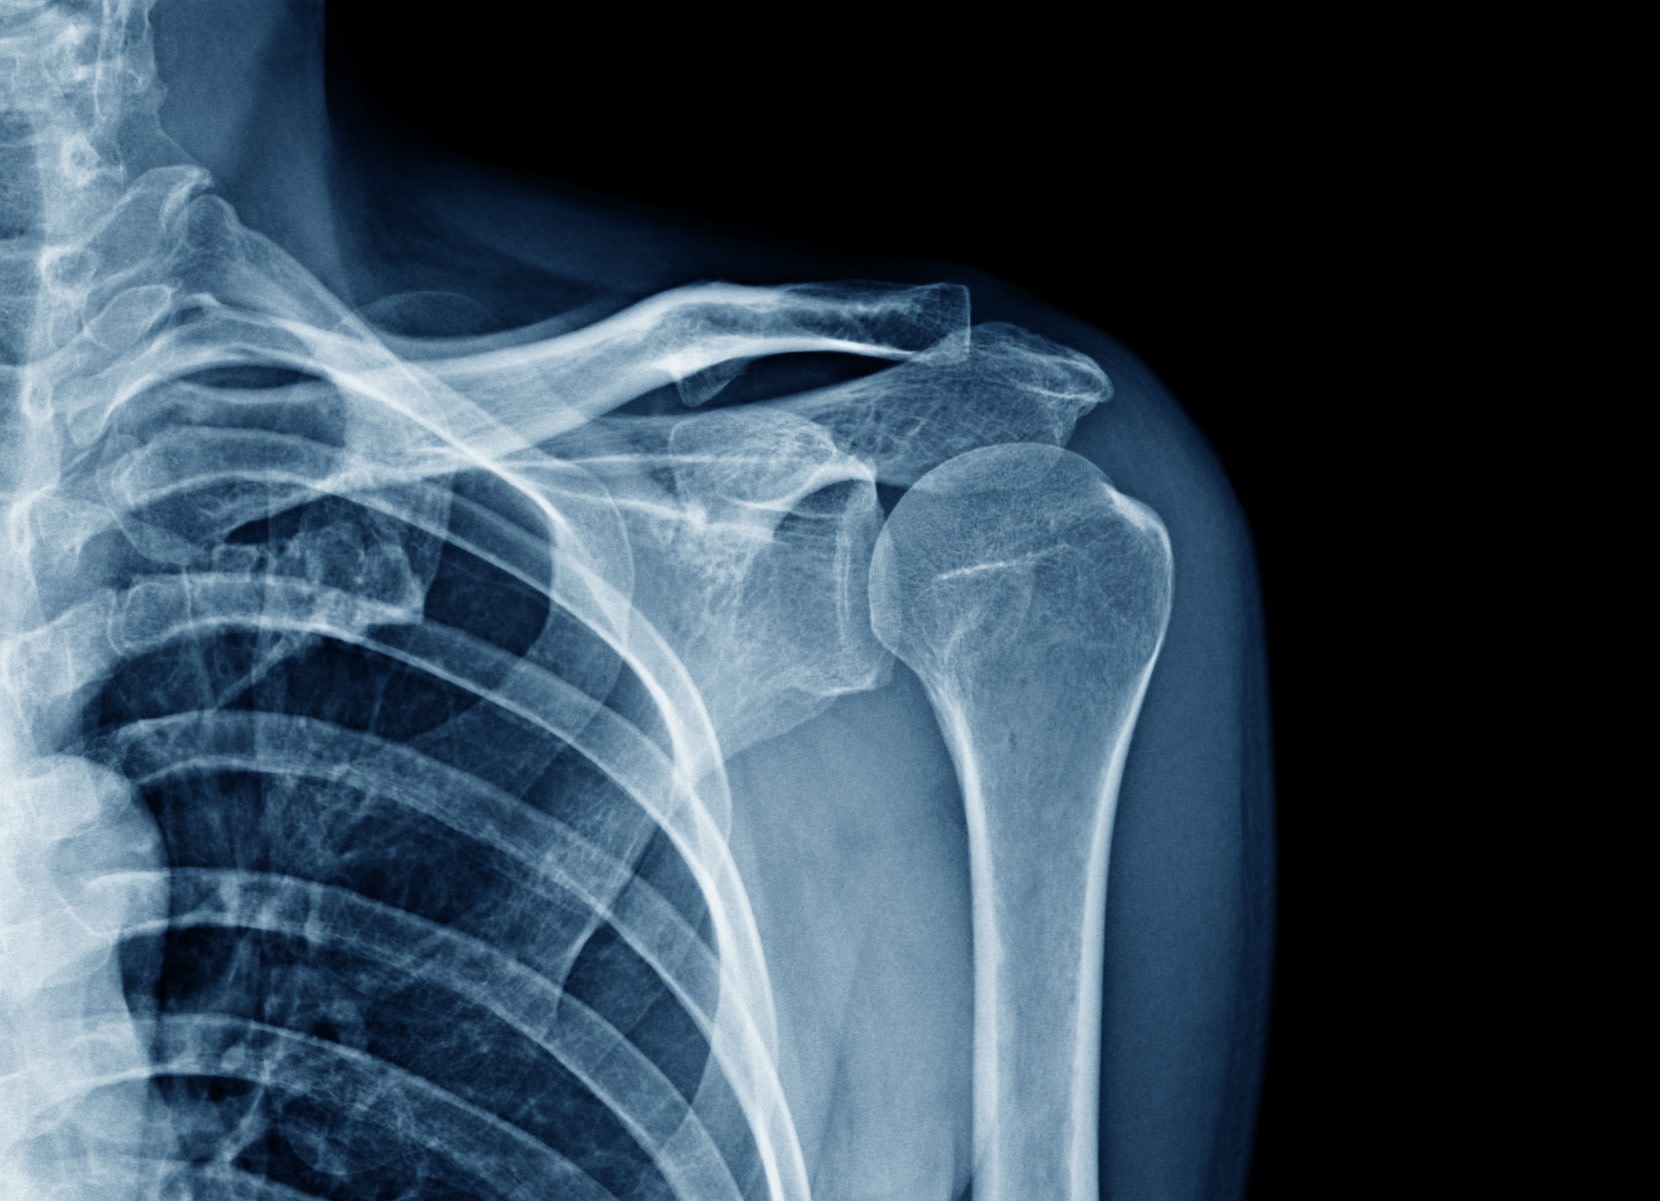

Il faut consulter un spécialiste, souvent un chirurgien orthopédiste, pour un bilan comprenant radiographie et échographie.

Comment se fait le diagnostic ?

Un médecin de l'hôpital Saint Martin de Pessac près de Bordeaux pourra réaliser un examen clinique, puis prescrit des examens d’imagerie comme une radiographie, une échographie ou une IRM pour visualiser les tissus et confirmer le diagnostic.